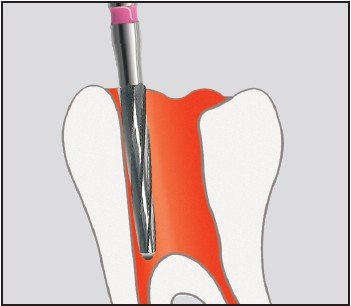

Edenta H152 - endodontické nástroje, extra dlhý kónus Endobur - 5 ks

| Kategorie | Ordinace > Endodoncie > Endo nástroje > Kořenové nástroje > H-File (Protahováčky Hedström) |